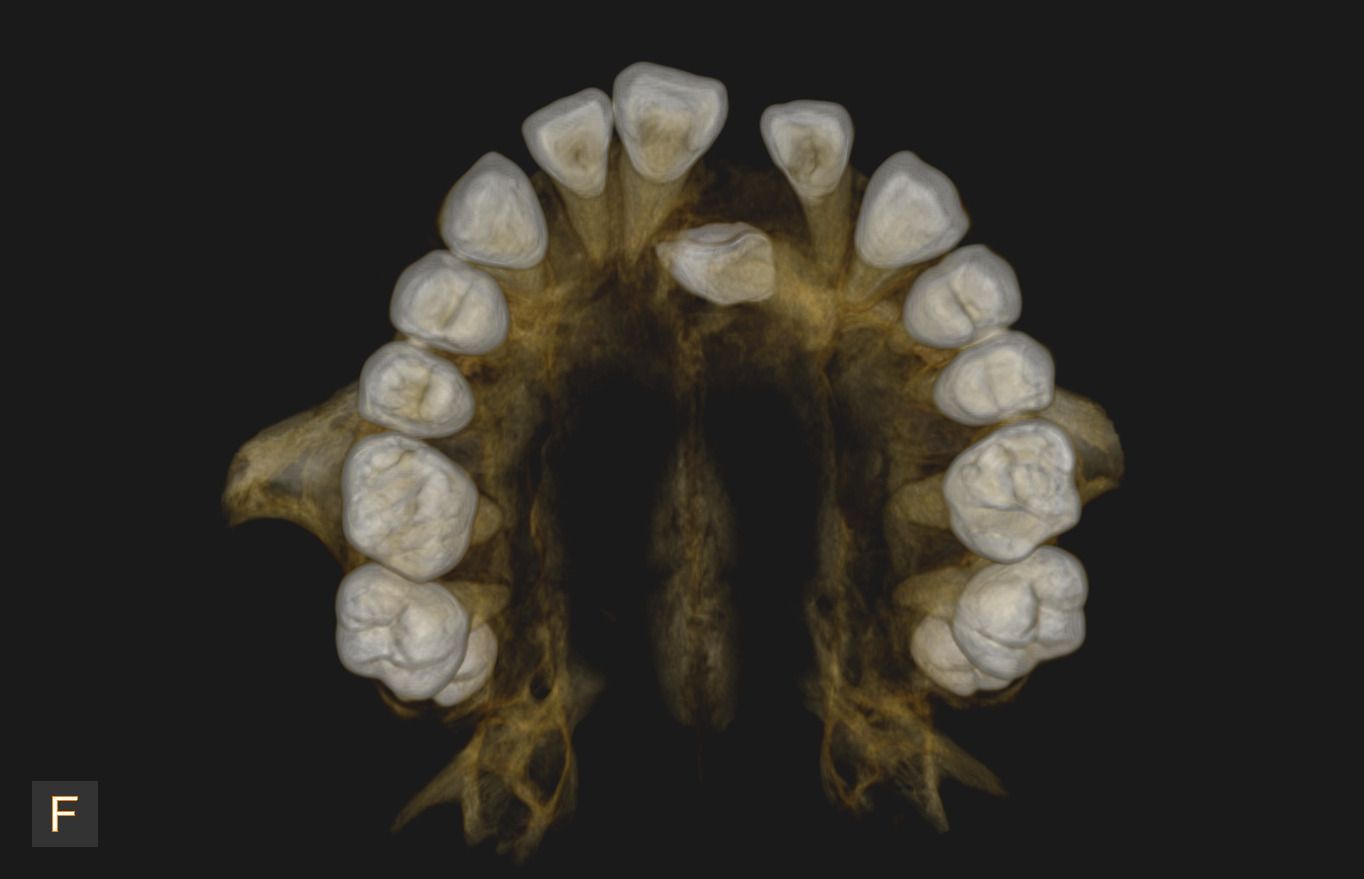

Uno de nuestros principales servicios es la adquisición de imágenes dentales 2D y 3D, fundamentales para un diagnóstico preciso y una planificación adecuada de tratamientos dentales.

Contamos con tecnología avanzada que nos permite obtener imágenes claras y detalladas de la boca y los tejidos circundantes, lo que es crucial para evaluar la salud dental y detectar posibles problemas.